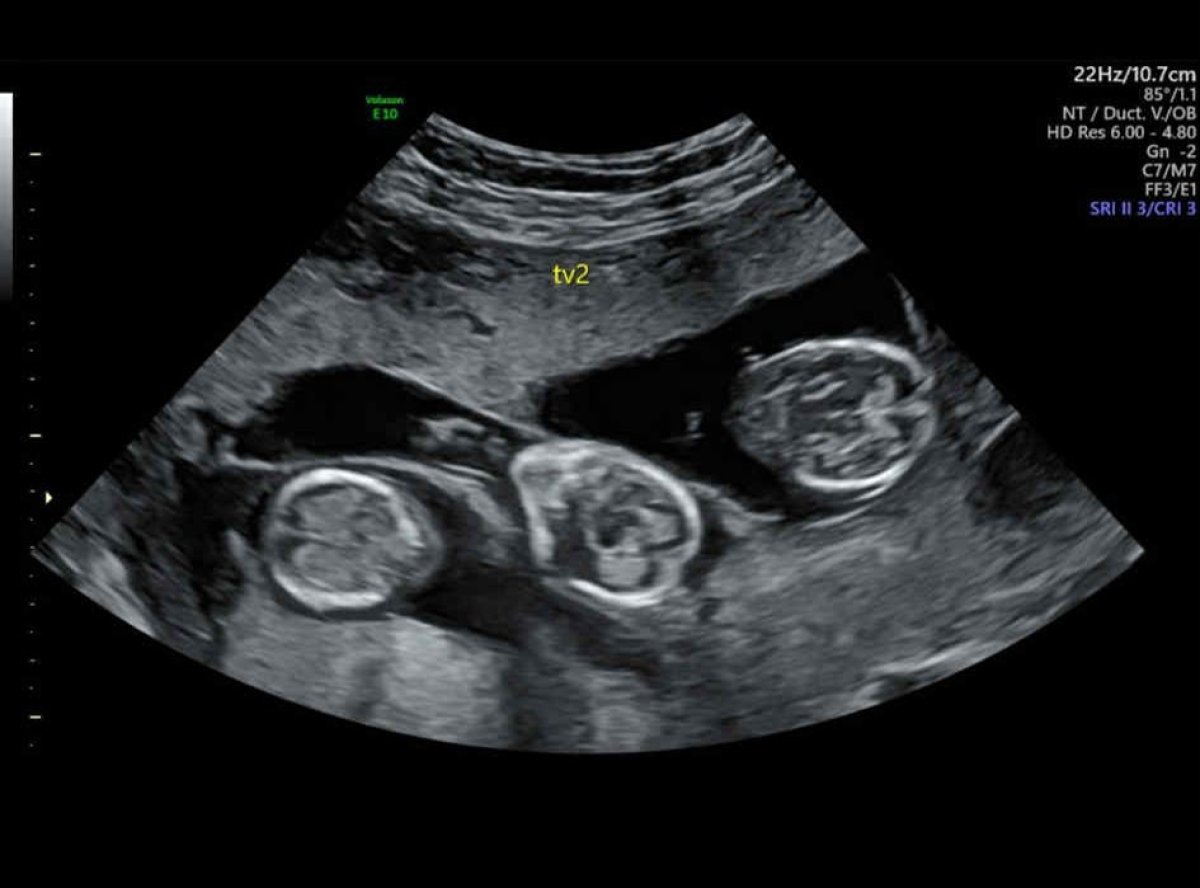

Со оглед на возраста, не очекувале брз успех, па во текот на процедурата биле пренесени три ембриони за да се зголемат шансите. Иако лекарите ги предупредувале на ризиците и советувале редукција, Мари решила да му верува на својот инстинкт. На крајот, се прифатиле сите три ембриони.

Тројките биле родени со итен царски рез, што била единствената разлика во однос на претходните породувања што ги имала по природен пат. Момчето тежело 1,5 килограми, едно девојче 1,3 килограми, а другото само еден килограм.